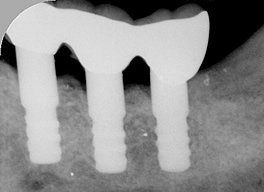

| 作製したインプラントのかぶせ | 同部のX線画像 |